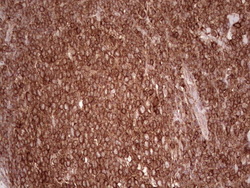

- Immunohistochemical staining of paraffin-embedded Human lymphoma tissue using anti-WIBG mouse monoclonal antibody. (Heat-induced epitope retrieval by 1 mM EDTA in 10mM Tris, pH8.5, 120C for 3min, TA806496)

- Validation comment

- IHC